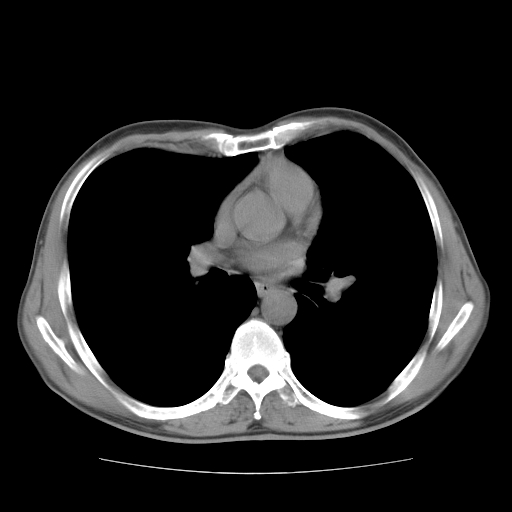

以下是引用drzhang8888在2008-11-20 22:20:00的发言:[br]密集的短毛刺,血管集束,胸膜凹陷,周边型肺癌可能性大,另双肺多发磨玻璃影,考虑感染

以下是引用流浪星在2008-11-20 22:28:00的发言:[br]左肺上叶近外围区见一类圆形结节影,毛刺征、胸膜尾征阳性,临近肺组织见多发渗出灶。考虑1,炎症性病变。 2.周围性肺癌。建议抗炎治疗后复查。

以下是引用qc80012345在2008-11-21 5:53:00的发言:[br]支持;周围型肺癌诊断。增强扫描。